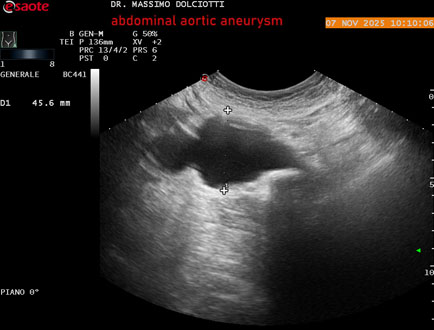

Data inserimento: 02/10/2023

Ecografia del: 23/09/2023

Strumento: Esaote MyLab Eight

Sonda: Convex Multifrequenza 1-8 MHz e Volumetrica

Età Paziente: M 84 anni

Motivazione dell'esame: dolore dolore al fianco destro, irradiato in basso, disuria, nicturia, stipsi, incremento volumetrico dell'addome.

Commento all'esame: le immagini ed il video documentano l'aneurisma dell'aorta addominale, esteso, con diametro antero-posteriore massimo documentato di 52 mm.

Conclusioni: aneurisma dell'aorta addominale (abdominal aortic aneurysm).

In collaborazione: Dr. Emanuele Fiorini - Ancona

Presentazione: Dr. Massimo Dolciotti - Ancona